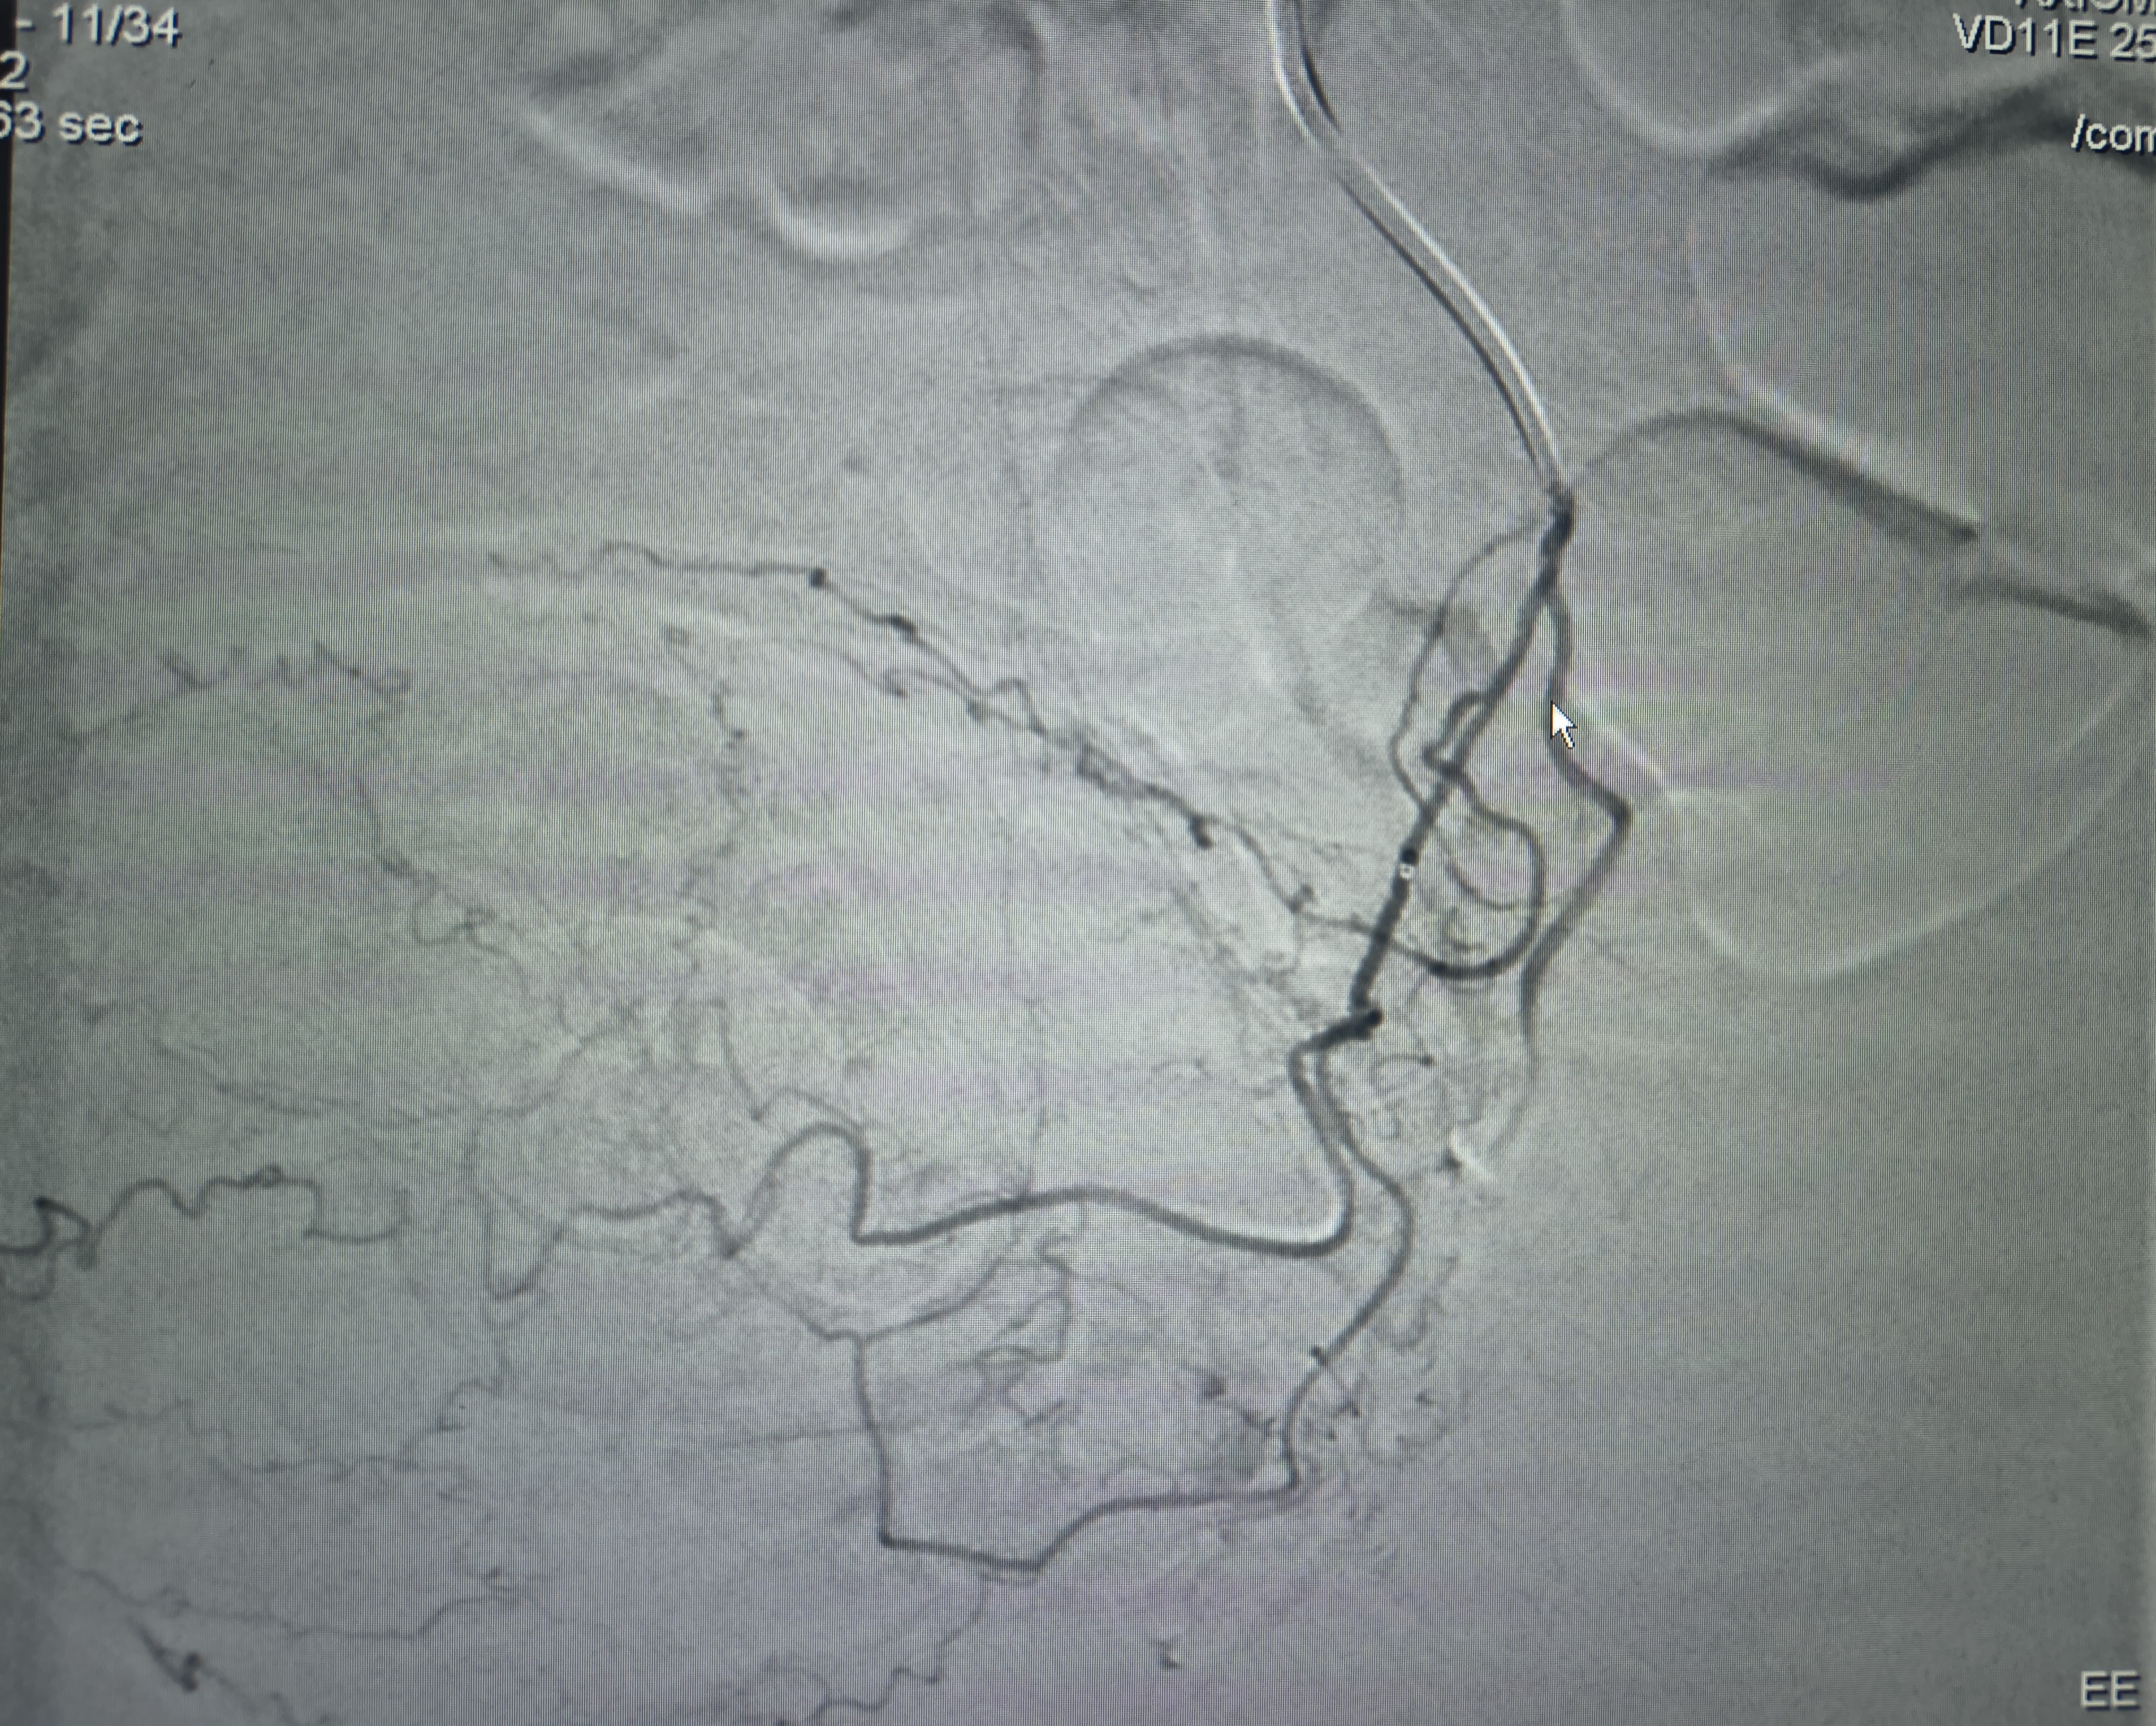

AVM embolisation